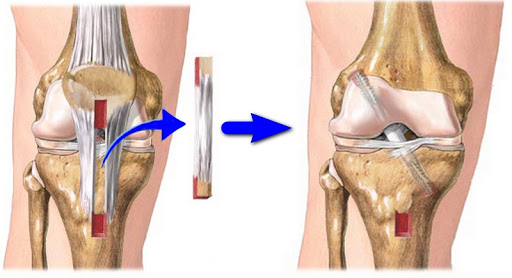

Хирургическое вмешательство выполняется при неэффективности проводимого ранее консервативного лечения. Второе показание — полный разрыв связки.

Суть операций заключается в восстановлении целостности сухожилия или связки. Накладывается П-образный шов, иногда несколько. Если же разрыв или растяжение старое, и при этом структура связки выраженно разволокнена, то используют аутоткани или алло-материалы.

После проведения операции необходима длительная фиксация конечности для восстановления структуры сшитой связки. Рекомендуемая позиция конечности — сгибание в колене на 150 градусов. Время иммобилизации — 4 — 6 недель.

Связки коленного сустава (анатомия их хорошо изучена) могут быть подвергнуты реконструктивному лечению. Операции могут ограничиваться обычным сшиванием разорванных связок. Но сегодня можно использовать и более современные методики, материалы.

Реконструктивные операции заключаются в том, чтобы сшить множество разорванных лоскутов между собой, а некротизированные участки ликвидировать. В рамках аутотрансплантации используют собственные ткани, участки. А при аллотрансплантации применяются биологические материалы доноров. Возможно, от трупного материала.

При отрывах сухожилий от костных структур используются различные фиксаторы.